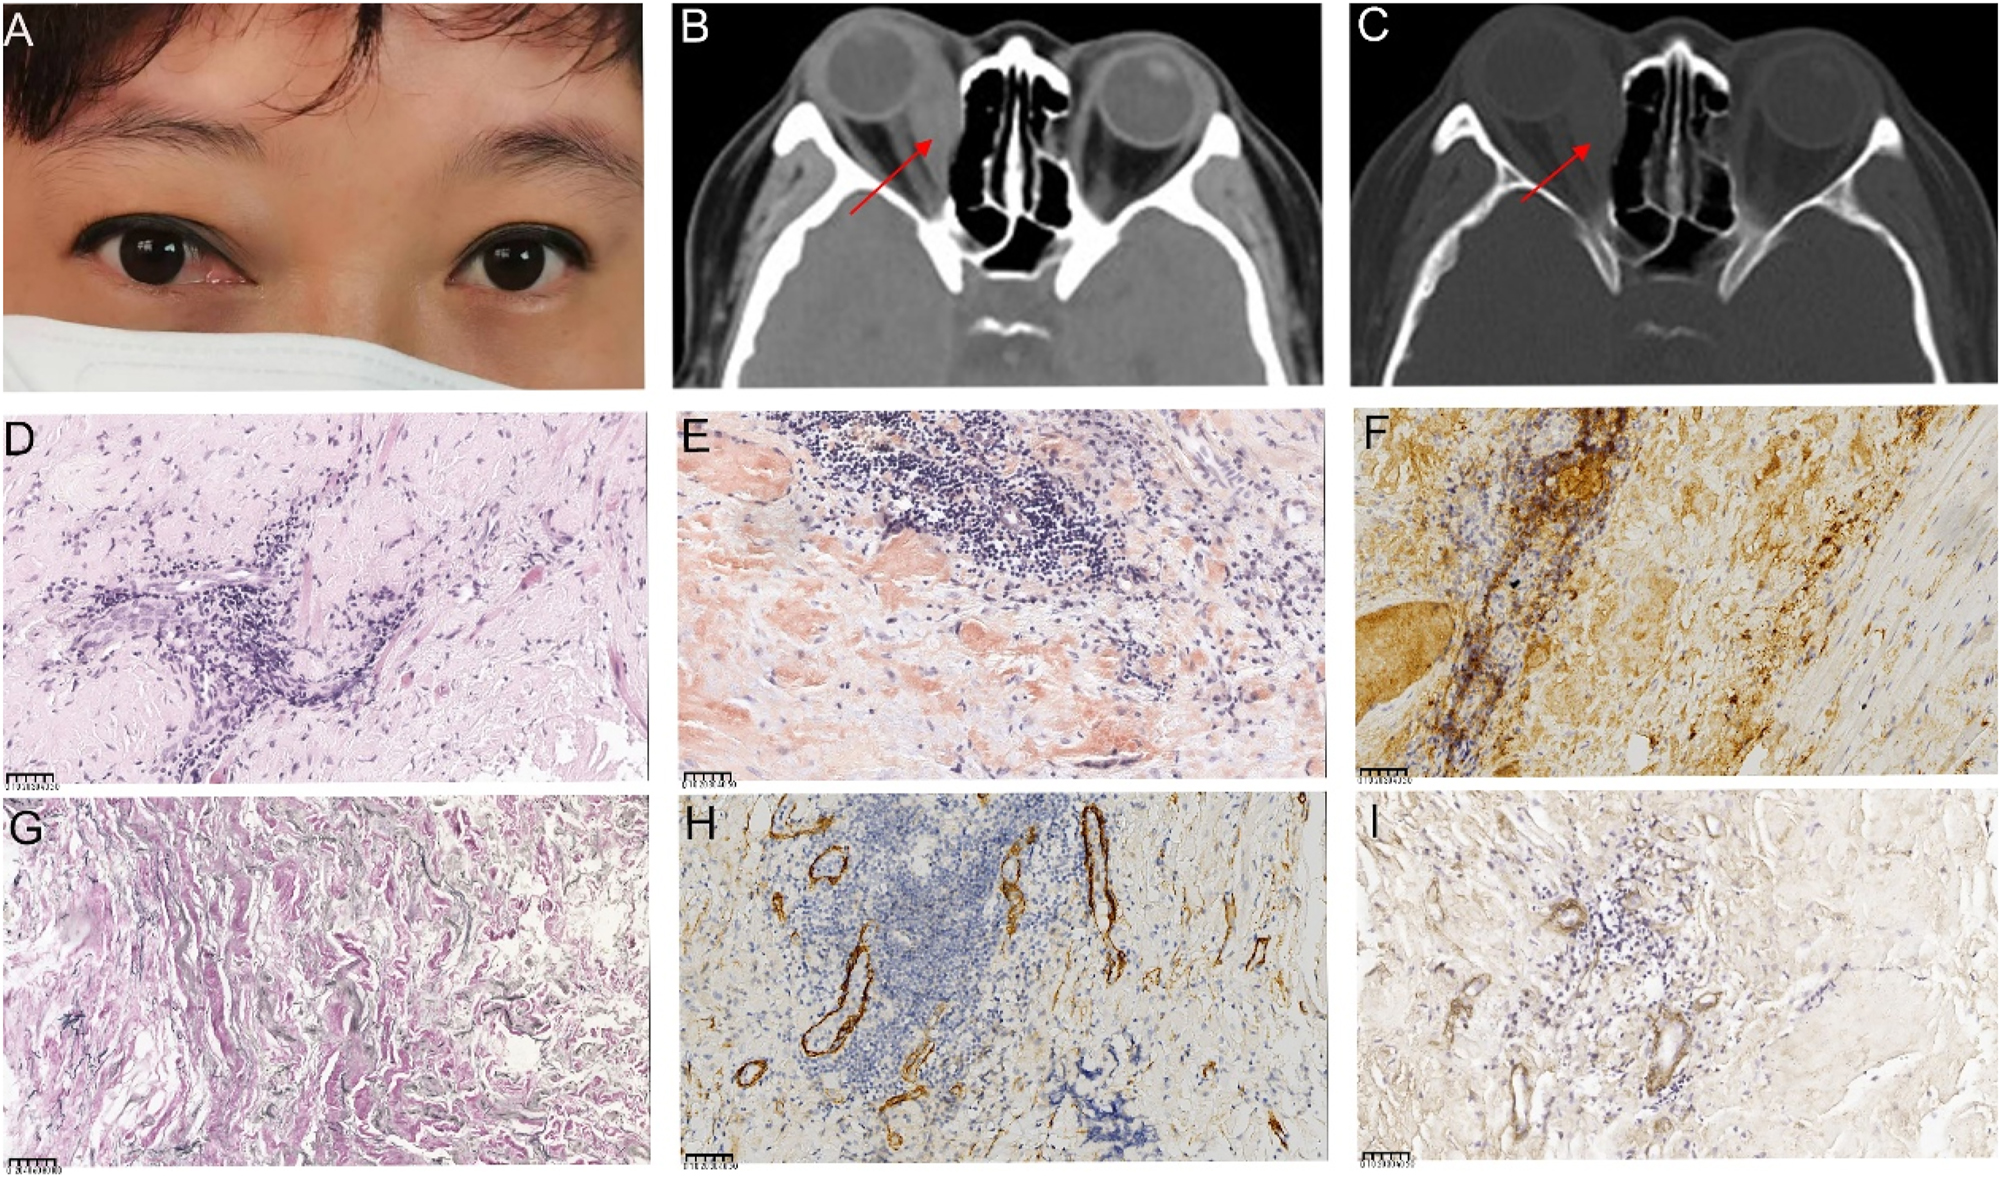

A 41-year-old woman presented with a 1-year history of right eye proptosis and restricted ocular motility. The patient’s visual acuity was 20/40 in both eyes, and the right eye exhibited pronounced proptosis, limited motility in horizontal directions, and bulbar conjunctival congestion and edema (Figure 2A). Computed tomography (CT) scan revealed fusiform enlargement of the right medial rectus muscle, whereas the tendons remained unaffected (Figure 2B and C). The pathological diagnosis indicated amyloidosis, with a significant increase in IgG4-positive cells (Figure 2D–I). The patient’s recent serum IgG4 level was 0.944 g/L, which was within the reference range of 0.03–2.01 g/L. The patient did not undergo any treatment regimen and was advised to attend regular follow-ups. One year later, the patient exhibited further enlargement of the medial rectus muscle of the right eye (Figure 2A), accompanied by a decline in visual acuity to 20/50 in the affected eye. Orbital contrast-enhanced magnetic resonance imaging (MRI) revealed an enlarged medial rectus muscle in the right eye with mixed intensity, and the maximum cross-sectional area of the tumor was approximately 2.92×1.43 cm (Figure 3A–D). A second surgical procedure was necessary, and the resected specimen appeared as hard, brittle, yellow-white masses (Figure 3E). Immunohistochemical staining (IHC staining) revealed 0–90 IgG4+cells per high-power field (HPF) in the lesion (Figure 3H). IHC staining confirmed MALT lymphoma, showing positive expression for CD20, CD3, CD5 (Figure 3I–M) and CD23 (FDC), and negative expression for CD10, Cyclin D1, CD1a, ALK, S100, Langerin, and BRAF V600E. Ki-67 staining indicated a low proliferative index of 5–10 % (Figure 3N). No clonal IgH and IgK rearrangements were detected. In addition, her serum IgG4 levels were within the normal range. Whole-body imaging revealed no signs of systemic disease. Consequently, a definitive diagnosis of orbital MALT lymphoma with primary amyloidosis was established. The patient underwent successful treatment with three-dimensional conformal radiotherapy (3DCRT), with a total dose of 30 Gy administered in 10 fractions using 6 MV photons. Follow-up orbital MRI one year later showed a significant reduction in tumor size, with the maximum cross-sectional area decreasing from 2.3×0.8 cm–2.3×0.57 cm (Figure 4A–C). However, fundus examination revealed macular edema in the right eye, for which the patient received a Dexamethasone Intravitreal implant (Ozurdex, Allergan Pharmaceuticals, Ireland). This condition may be a side effect of radiotherapy, and the patient remains under ongoing follow-up.

Ocular appearance, orbital imaging, and pathological images of the lesion specimen in the first surgery (A) Reoperative image showing proptosis along with congestion and edema of the medial bulbar conjunctiva in the right eye (B, C) computed tomography (CT) images show significant thickening and a clump-like appearance of the right medial rectus muscle, with slight calcification in the lower part. The right ethmoid sinus wall appears compressed and thinned. The red arrows indicate the right enlargement of the medial rectus muscle (D, E) pathological images of the specimen (D) high magnification showing muscle and fibroadipose tissue with interstitial lymphocytic infiltration (hematoxylin and eosin (HE) 400×), (E) Congo red staining of the orbital lesion, demonstrating a positive result under microscopy at 400× (F) HC staining shows over 40 IgG4+cells per high-powered field (HPF) in the lesion (400×) (G) positive elastic fiber immunostaining of lesion cells (200×) (H) Partial positive smooth muscle actin immunostaining of lesion cells (400×) (I) partial positive IV collagen fiber immunostaining of lesion cells (400×). The unit of scale bar is μm.